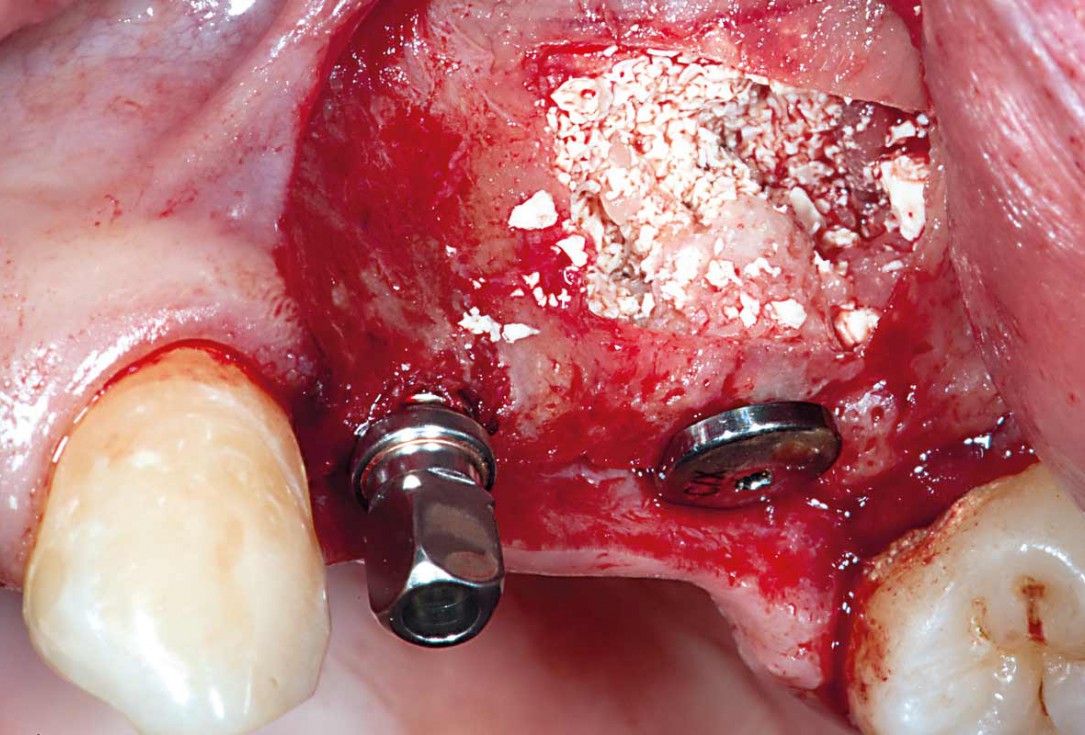

Periimplantitis treatment with maxgraft® bonering - Dr. B. Giesenhagen

Severe periimplantitis at tooth 15 with bone loss up to 1/3 of the implant